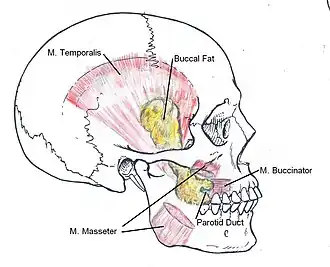

Buccal fat-pad reduction: The anatomic locale of the buccal fat pads in the human face.

Buccal fat-pad reduction: The anatomic locale of the buccal fat pads in the human face. -